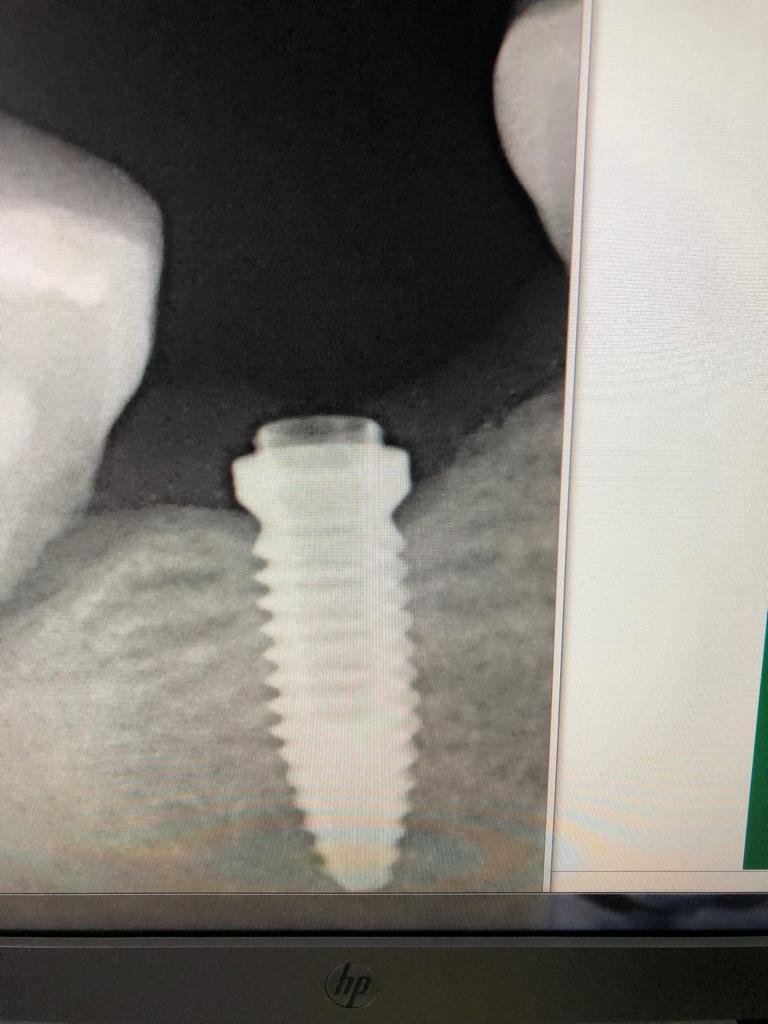

Buenos días Perdón por la calidad de las fotos He probado varios transfer y no consigo dar con el correcto ¿podríais ayudarme? Muchas gracias